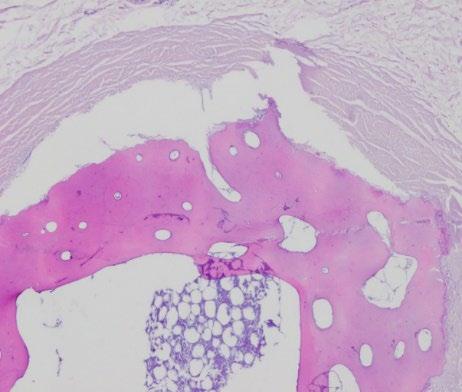

Komórki, które odgrywają najistotniejszą rolę w rozwoju PVR: RPE, glejowe Müllera, fibroblasty i makrofagi [12].

Proces PVR rozpoczyna się na krawędzi przedarcia. Można podzielić go na kilka faz, przypomina nieprawidłowe gojenie tkanki po przedarciu i odwarstwieniu siatkówki. Zauważono, że PVR nie występuje w wysiękowym odwarstwieniu siatkówki, można więc zakładać, że to przedarcie w RRD stanowi punkt startowy dla kaskady procesów prowadzących do powstania błon PVR. Natychmiast po odłączeniu się siatkówki neurosensorycznej od odżywiającej ją naczyniówki następuje niedokrwienie, miejscowe zapalenie i postępująca apoptoza fotoreceptorów. Dochodzi do przerwania bariery krew–siatkówka, co pozwala na swobodny napływ czynników chemotaktycznych i mitogennych, inicjujących przejście nabłonkowo-mezynchemalne komórek nabłonka barwnikowego (epithelial-mesenchymal transformation, EMT). W dalszej kolejności następuje nasilenie migracji i proliferacji, a w końcu procesy zwłóknieniowe i skurcz wytworzonych błon siatkówkowych (ryc. 1) [13].

przedarcie i odwarstwienie siatkówki

obkurczanie się błon

niedokrwienie i stan zapalny

proliferacja, migracja, transformacja

apoptoza

Rycina 1. Schematyczne przedstawienie następujących po sobie kluczowych faz patogenezy PVR

Proces ten, czyli EMT, może zachodzić zarówno w warunkach fizjologicznych, np. embriogenezie i gojeniu się ran, jak i w patologicznych – nowotworach i włóknieniu tkanek. Przejście nabłonkowo-mezynchemalne komórek nabłonka barwnikowego charakteryzuje się utratą biegunowości wierzchołkowo-podstawnej, zamianą ekspresji cytokeratyn na wimentynę oraz zwiększoną ruchliwością komórek i ich zdolnością do inwazji [36, 37, 38, 39, 40]. Komórki Müllera również odgrywają istotną rolę w rozwoju PVR, głównie poprzez wydzielanie cytokin i czynników wzrostu, prowadząc do glejozy i proliferacji [41]. Opisuje się, że przechodzą one również transformację glejowo-mezenchymalną pod wpływem TGF-β [42, 43].

Faza obkurczania się błon

Po odwarstwieniu stransformowane w EMT komórki nabierają cech miofibroblastów. Synteza włókien pośrednich aktyny stymulowana jest przez IL-1 i odbywa się w trakcie EMT. Alfa-aktyna mięśni gładkich jest stymulowana do wytwarzania filamentów, a następnie aneksyna A2 inicjuje skurcz włókien miofibroblastów. Aktywacja komórek Müllera prowadzi do wyraźnej glejozy w obrębie siatkówki, która prowadzi do jej zesztywnienia i skrócenia [44]. Skracanie się błon PVR powiększa obszar odwarstwienia i uwalniając kolejne RPE do szklistki nasila tworzenie się nowych błon. W przeciwieństwie do skurczów miocytów, miofibroblasty mogą utrzymywać skurcz przez dłuższy czas [37].